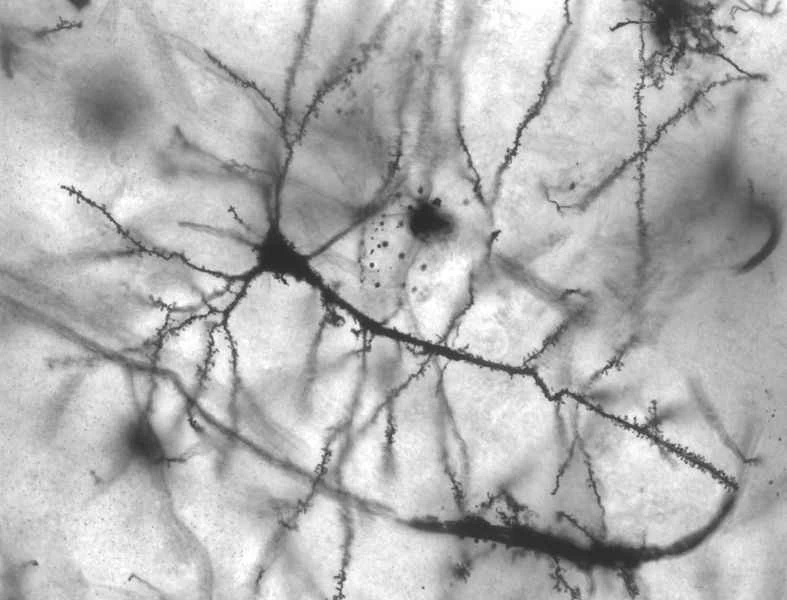

從化學角度來說,二氧化碳加入水中會生成碳酸,而碳酸會被味覺細胞感知到。研究表明,一種名為碳酸酐酶的酶存在於這些細胞上,並與碳酸發生反應,從而產生碳酸水熟悉的「劈啪」聲。 (有趣的是:服用抑制這種酵素的高山症藥物的登山者,如果再喝香檳,會感覺香檳有股洗碗水的味道。)這種酵素與人體三叉神經發生的某種反應相結合,可能就是碳酸水獨特口感的來源。但如果你是個研究人類味覺習慣的外星人(為了即將到來的食物入侵?),你可能會覺得碳酸水簡直令人作嘔:因為碳酸飲料中的二氧化碳會刺激疼痛感受器。